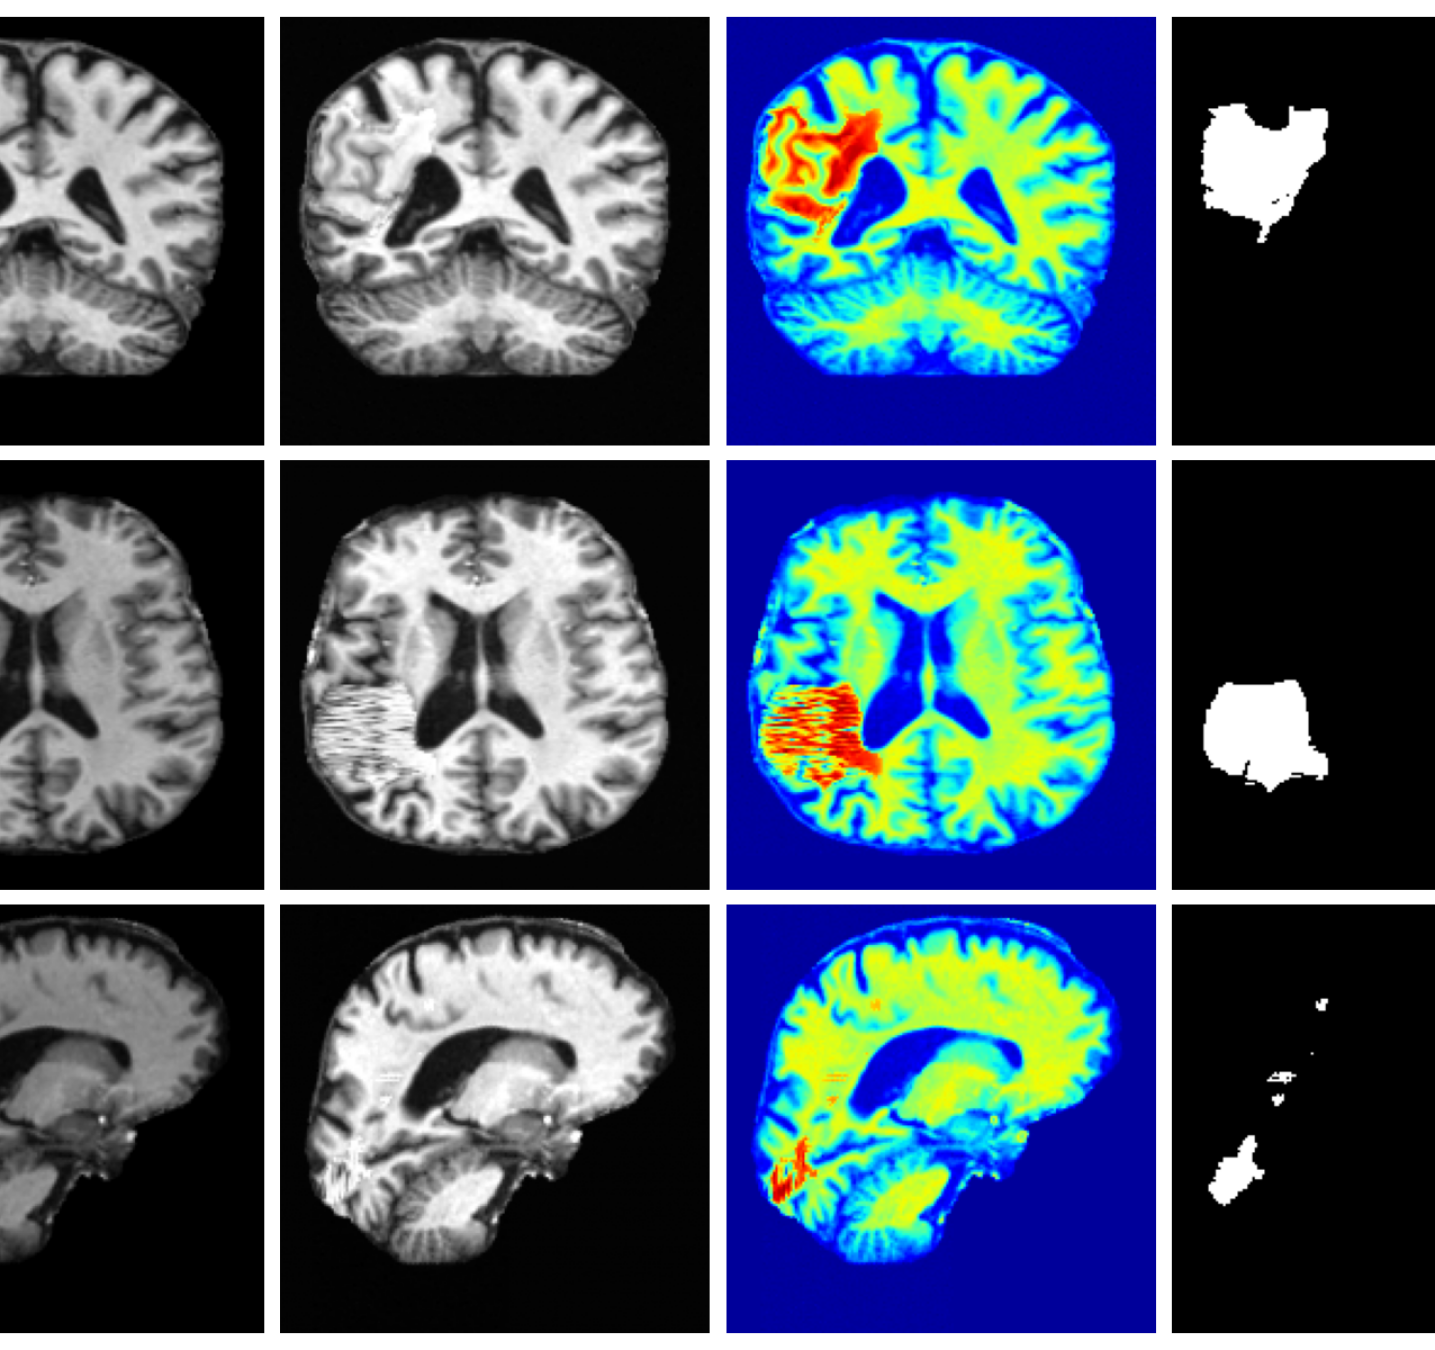

Qualitative T1w results are shown in Figure 2, with further examples for other modalities in Appendix A.8. LoHiResGAN and Res-SRDiff produce unrealistic images with severe artifacts, likely arising from bias fields, sharp intensity artifacts, and other noise not present during training. UniRes generates oversmoothed images, likely due to its TV prior and its reliance on information from multiple input modalities, whereas we apply it unimodally. Di-Fusion shows less pronounced but still notably blurry, voxelated reconstructions which lack the fine-grained details generate by our method. This is likely, in part, due to our use of synthetic rather than real noisy training data, which the method was designed for. As such data is scarce, and in our case unavailable, this requirement represents a significant limitation of Di-Fusion. SynthSR, whilst not as well as our method, does preserve key anatomical structures. However, our difference maps show reduced contrast, further supporting the strong quantitative results shown in Table 2.

Figure 3 (additional examples in Appendix A.9) shows that SynthSR preserves healthy tissue but struggles with large lesions, while DDPM-2D and DDPM-3D, despite producing high-contrast anomaly maps, generate unrealistic homogeneous inpainting, consistent with their lower performance in Table 3. In contrast, our method yields the most anatomically plausible inpainted regions, although anomaly maps appear subtle due to low contrast between lesions and healthy tissue.